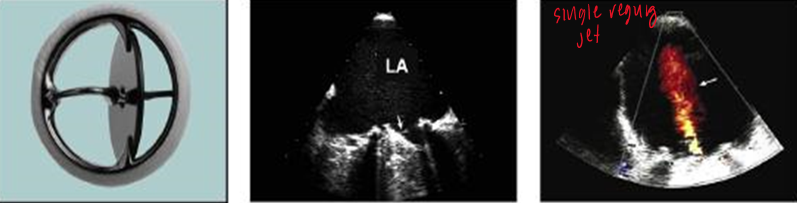

what is this?

bileaflet (st jude)

how many orifices do prosthetic bileaflet (st judes) valves have?

3 orifices (3 color jets)

where do we sample velocities?

there are 2 large orifices and one smaller.

sample flow from the smaller orifice with higher velocities